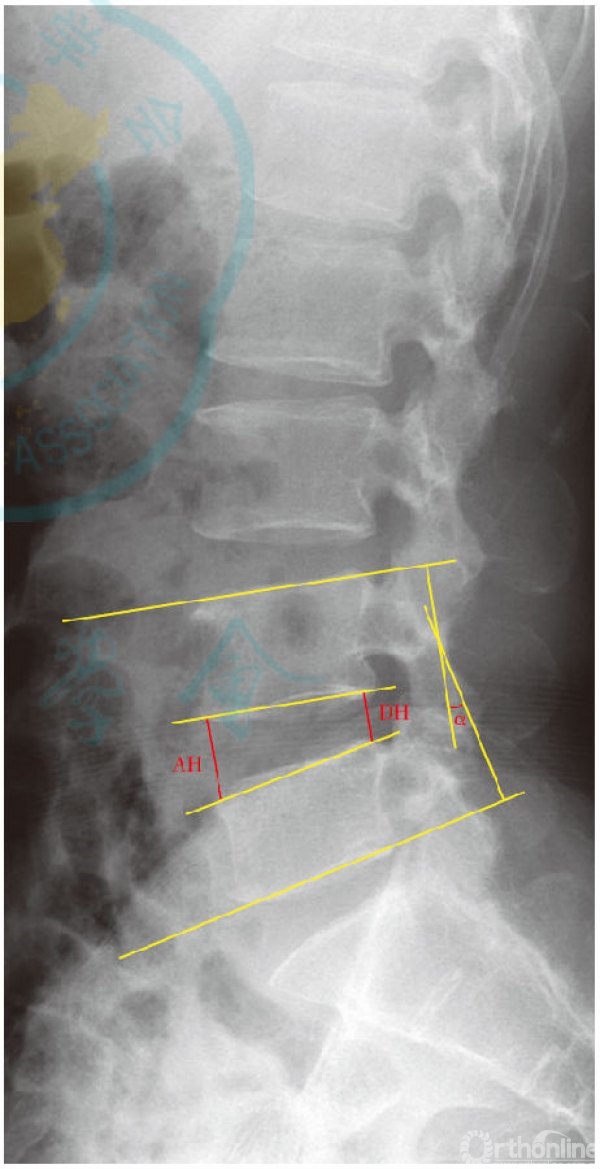

随访过程中摄腰椎正侧位及过伸过屈位X线片并测量手术节段以及邻近节段椎间高度。椎间高度取术前、术后各次随访的腰椎侧位X线片上椎间隙前后缘高度的平均值(本研究中双节段患者椎间高度取双节段高度平均值,图1)。通过测量手术节段椎间高度评估是否存在终板塌陷等手术并发症、椎间孔是否得到间接减压以及腰椎正常生理弧度和力线关系是否恢复,邻椎椎间高度可进一步评估椎间盘退变情况。

②活动度

活动度(range of motion,ROM):随访过程中通过测量腰椎正侧位及过伸过屈位X线片手术节段及邻近节段Cobb角来评估腰椎活动度(图1)。活动度的大小能够帮助评估腰椎屈伸等活动功能。

图1 椎间高度及活动度测量方法示意图。椎间高度:以腰椎侧位X线片椎体前缘高度AH与后缘高度DH的均值表示椎间隙高度;活动度:测量腰椎正侧位及过伸过屈位X线片手术节段及邻近节段Cobb角α表示腰椎活动度